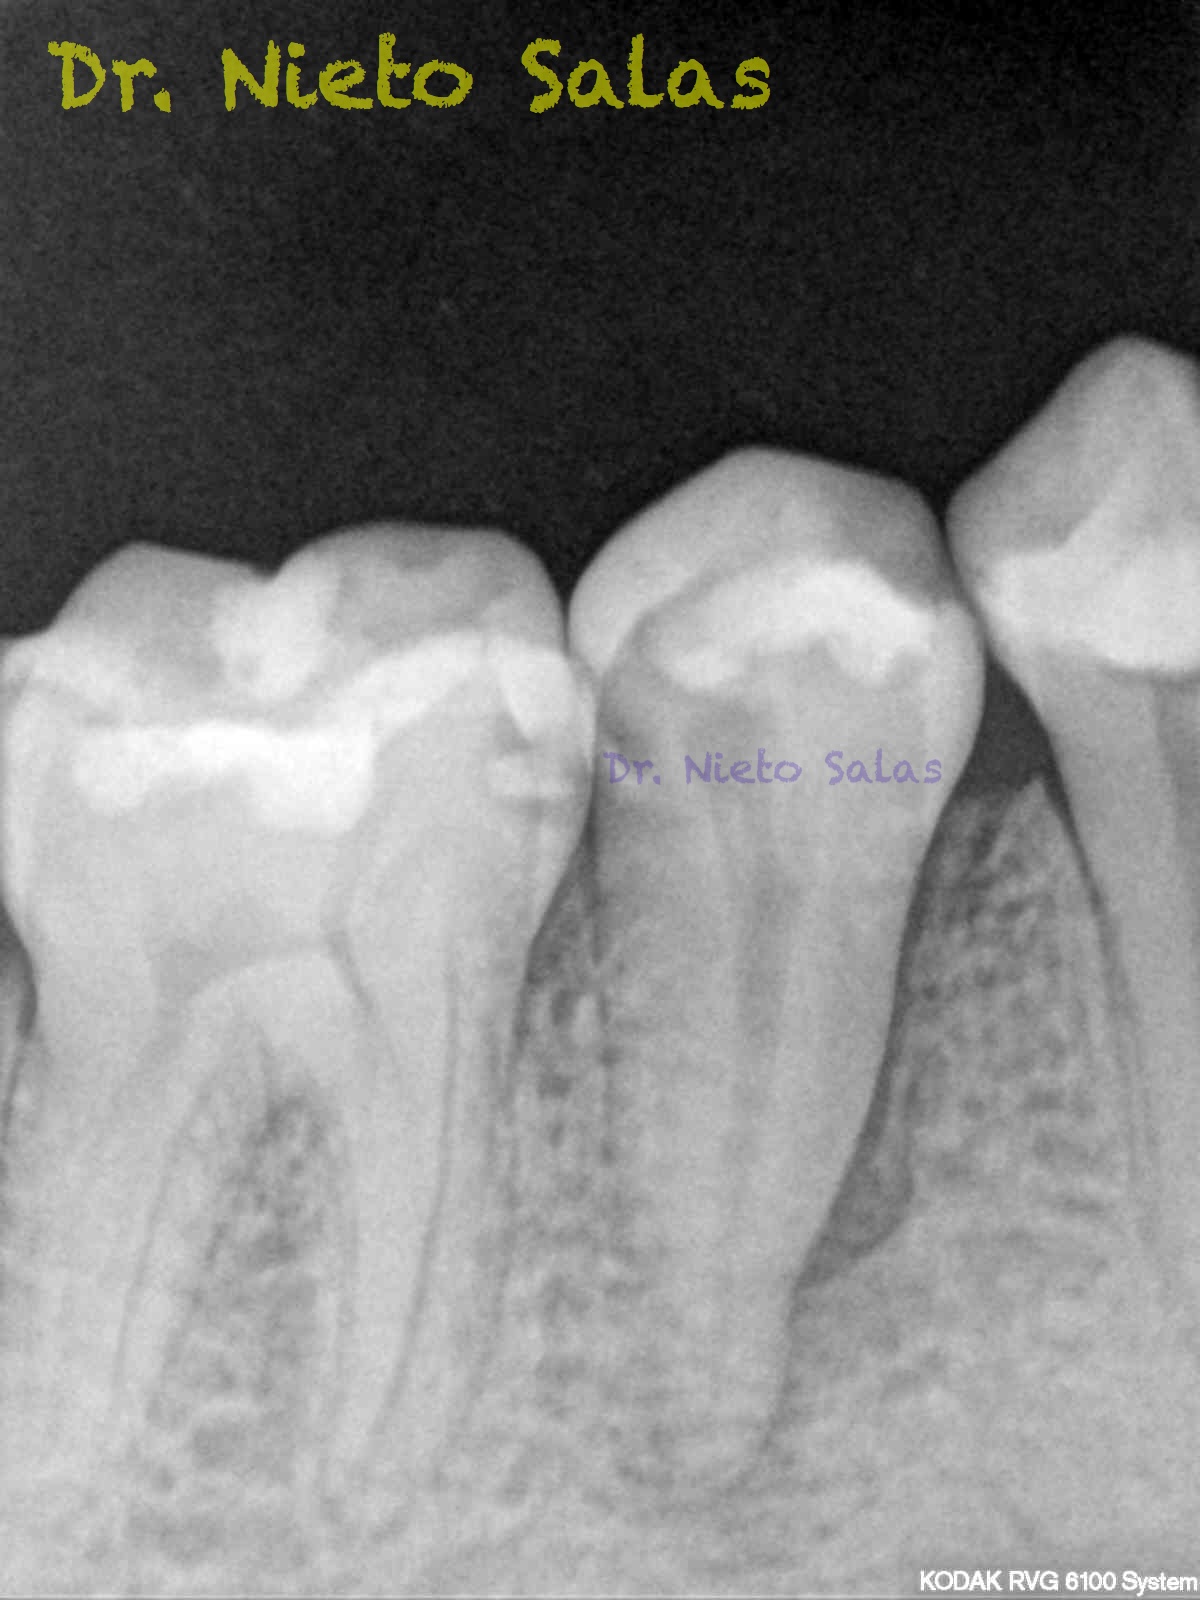

Nos llega a la clínica  este 4.5 con necrosis y periodontitis apical. la instrumentación se realizó con técnica de crown-down con limas K3 (SybronEndo) y la obturación con la técnica de ola continua de Buchanan, el tiempo de trabajo (para mi bastante importante) sobre 70-90 min.

Pero no todo se va a dejar al «poder de la irrigación»,  es muy importante la biomecánica, y la intuición para poder instrumentar esos pequeños conductos laterales que es muchas ocasiones nos dan problemas. Así, pues, os pongo un par de casos que con ayuda de esta «intuición» pudimos hacer un buen tratamiento.

Presentaban un sondaje normal, y sospechamos de que podía tratarse de lesiones por conductos laterales.

Una vez que hemos desbridado biomecánicamente con limas de muy pequeño diámetro, obturamos: